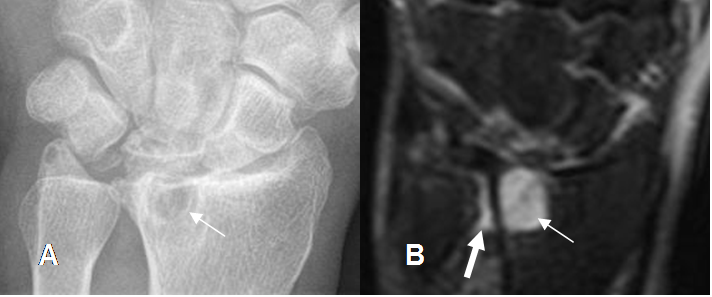

Fig 101. Artropatía degenerativa.

A: Rx AP y B: RM coronal en STIR. Cambios degenerativos en la articulación radiocarpiana, con formación de quiste subcondral. Adicionalmente en la RM se observa líquido en la articulación radioulnar distal, signo indirecto de ruptura en el complejo del FCT. (Flecha grande).